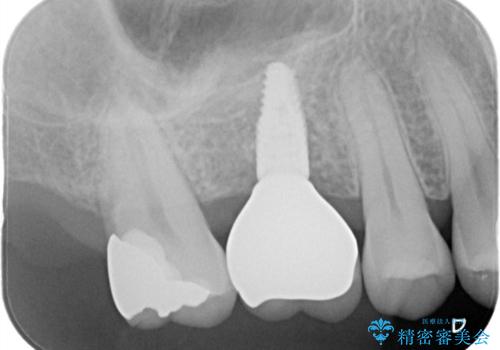

インプラントとブリッジ治療の2通りの治療方法のご提案をさせていただき、インプラント治療をすることとなりました。

インプラントを埋入する際に骨の高さが不足していたので、骨造成も同時に行う計画としました。

インプラント治療はブリッジと比較して、両隣の歯を削らなくてもよいというメリットがあります。

今回は両隣の歯を削りたくないとの希望がありましたので、インプラント治療を選択されました。